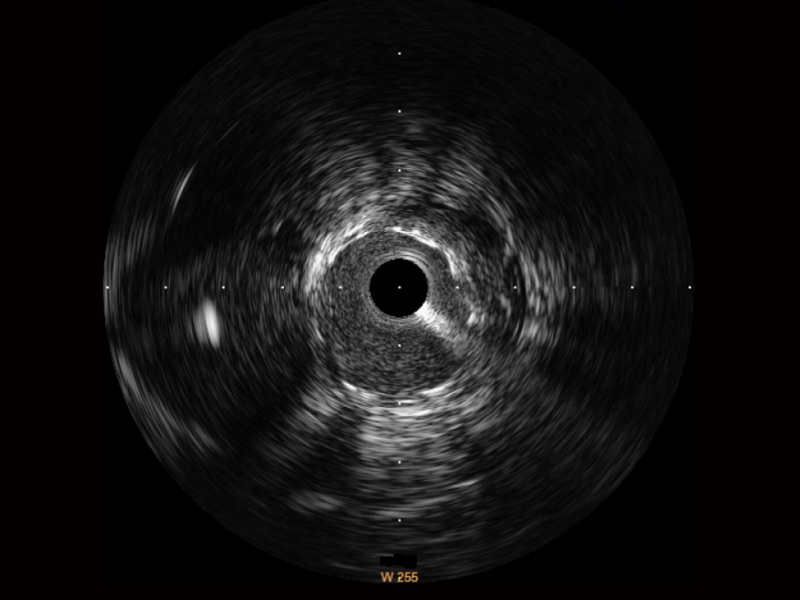

DB中国旗舰官方网站宽频IVUS图像

对比传统IVUS导管成像,DB中国旗舰官方网站宽频IVUS图像的近场支架梁显影更细腻,远场中膜外血管仍清晰可辨,兼顾远中近,兼顾分辨力与穿透深度